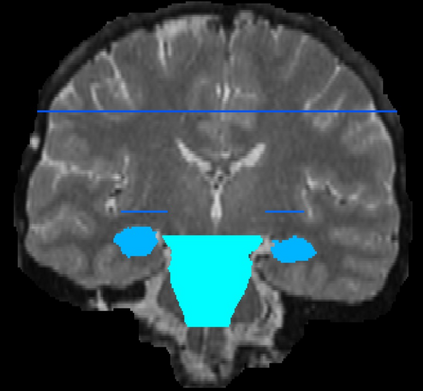

Imaging markers of cerebral small vessel disease provide valuable information on brain health, but their manual assessment is time-consuming and hampered by substantial intra- and interrater variability. Automated rating may benefit biomedical research, as well as clinical assessment, but diagnostic reliability of existing algorithms is unknown. Here, we present the results of the \textit{VAscular Lesions DetectiOn and Segmentation} (\textit{Where is VALDO?}) challenge that was run as a satellite event at the international conference on Medical Image Computing and Computer Aided Intervention (MICCAI) 2021. This challenge aimed to promote the development of methods for automated detection and segmentation of small and sparse imaging markers of cerebral small vessel disease, namely enlarged perivascular spaces (EPVS) (Task 1), cerebral microbleeds (Task 2) and lacunes of presumed vascular origin (Task 3) while leveraging weak and noisy labels. Overall, 12 teams participated in the challenge proposing solutions for one or more tasks (4 for Task 1 - EPVS, 9 for Task 2 - Microbleeds and 6 for Task 3 - Lacunes). Multi-cohort data was used in both training and evaluation. Results showed a large variability in performance both across teams and across tasks, with promising results notably for Task 1 - EPVS and Task 2 - Microbleeds and not practically useful results yet for Task 3 - Lacunes. It also highlighted the performance inconsistency across cases that may deter use at an individual level, while still proving useful at a population level.